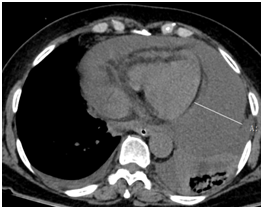

今年56岁的患者孙女士(化名)因一周来始终感觉中上腹部胀痛且伴随胸闷气短不适,由120转诊送往仁济医院嘉定分院救治。据当时急诊接诊医生、胸外科主治医师郭俊刚介绍,患者入院时不能平卧,气促明显,心率加快,中上腹部及右上腹部压痛明显,精神萎靡,处于焦虑惊恐状态。CT及彩超提示,患者为急性胰腺炎,已导致大量心包积液,根据心包脏壁层间距判断,积液量已大于500ml。

心包穿刺前

“大量心包积液将导致心力衰竭、肺换气障碍等一系列严重后果。且该患者为胰腺炎症感染,胆囊炎急性加重还将进一步增加心脏负荷。一旦突发心包填塞,随时都有心跳骤停猝死可能!”回忆起患者当时的病情,郭俊刚医生依然感到后怕。“患者4年前有过扁桃体鳞癌手术史,此次心包腔大量积液,来源性质不明,不排除肿瘤性或结核性可能。”

大量心包积液最有效、最直接的治疗措施就是心包穿刺引流。于是,郭俊刚与家属充分沟通后,立即在急诊局麻下行心包穿刺引流术,前后共引流出血性心包积液约2000ml。